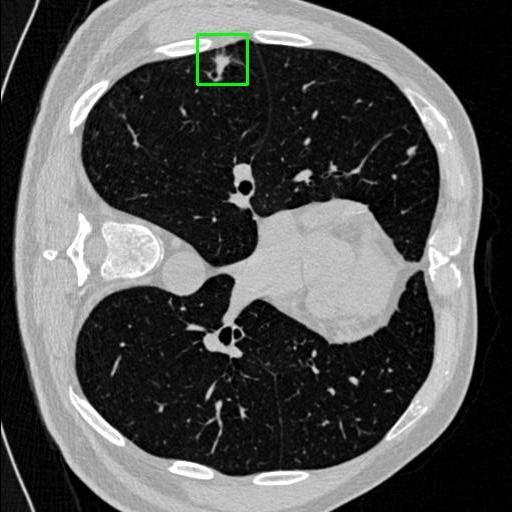

We developed an AI-based system using deep learning models for analyzing lung CT scans to detect and classify pulmonary nodules. We chose the YOLOv11 architecture for its enhanced object detection capability and adapted it specifically for medical imaging, incorporating pixel-level precision and severity classification.

Classification into three severity levels with colored bounding boxes.

Designed a severity classification system that categorizes nodules into null, moderate, and severe using colored bounding boxes, assisting in rapid clinical decision-making.